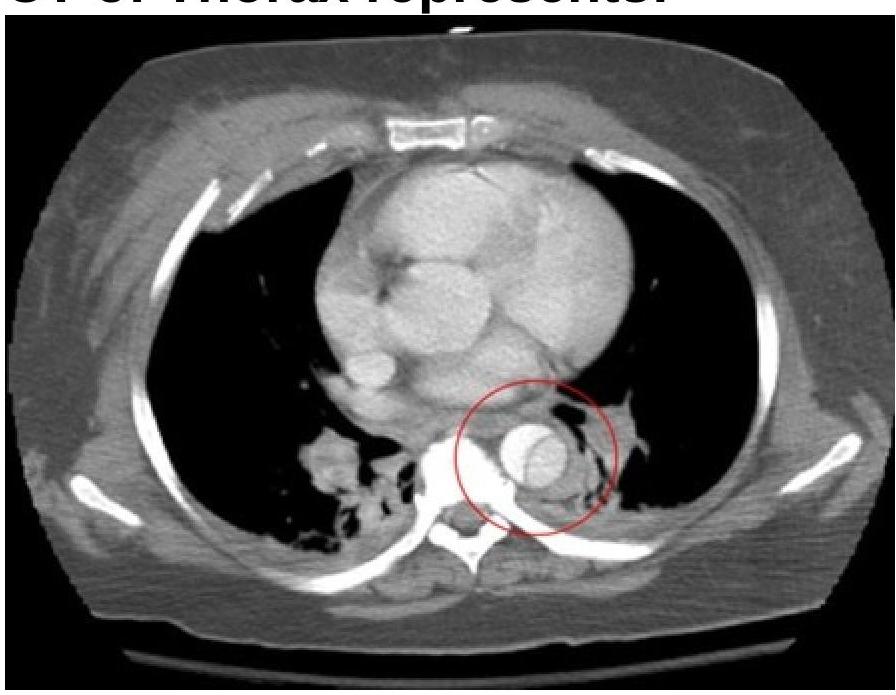

The CT thorax image shows:

Explanation: ***Ascending aortic dissection*** - The CT image shows a **classic intimal flap** separating the true and false lumens in the ascending aorta, which is the hallmark feature of an aortic dissection. - This represents a **Stanford Type A dissection** involving the ascending aorta, which is a life-threatening emergency requiring **immediate surgical intervention** due to high risk of complications including rupture, cardiac tamponade, and acute aortic regurgitation. - The presence of the intimal flap creating two distinct channels (true and false lumens) is pathognomonic for dissection. *Descending aortic dissection* - While the intimal flap is characteristic of dissection, the image specifically shows involvement of the **ascending aorta** (proximal to the left subclavian artery), not the descending thoracic aorta. - Descending aortic dissections (Stanford Type B) are typically managed **medically** with blood pressure control, unlike ascending dissections which require surgery. *Aortic aneurysm* - An **aortic aneurysm** represents focal dilatation of the aortic wall (>50% increase in diameter) without separation of the intimal layers. - While aneurysms can be a risk factor for dissection, the key finding here is the **intimal flap dividing the lumen**, which defines dissection rather than simple aneurysmal dilatation. - The image does not show the uniform circumferential enlargement typical of aneurysms. *Aortic coarctation* - **Aortic coarctation** is a congenital narrowing of the aorta, typically located at the aortic isthmus (near the ligamentum arteriosum), distal to the left subclavian artery. - CT would show focal narrowing with pre-stenotic dilatation and collateral vessel formation, not an intimal flap. - This is a completely different pathology without the characteristic dissection flap seen in this image.